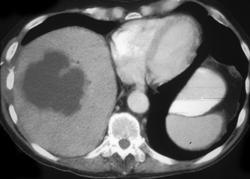

问题 女,35岁,右上腹痛、高热、白细胞计数升高,CT扫描如图,最可能的诊断是 ( )

选项 A、肝淋巴瘤 B、肝胆管细胞癌 C、肝脓肿 D、肝炎性假瘤 E、肝癌

答案 C